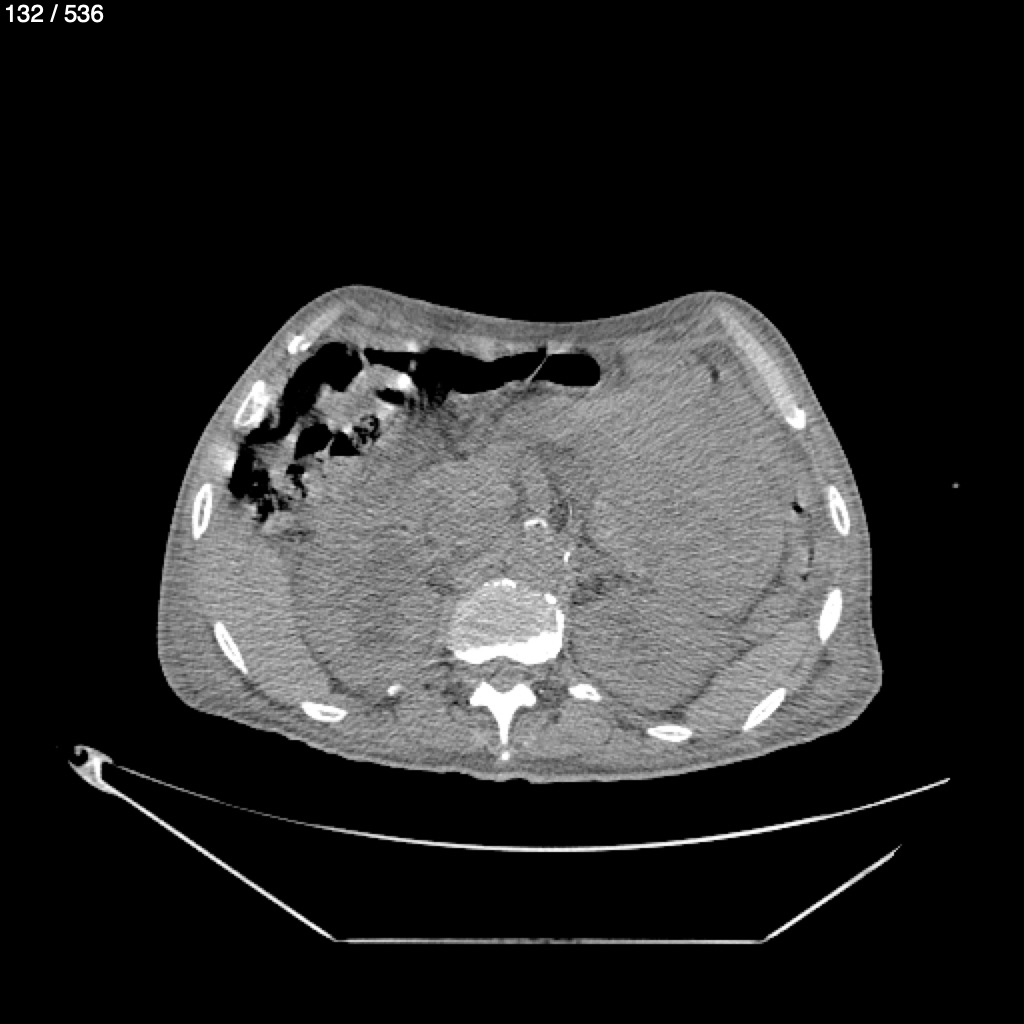

Angel Villalobos Palomeque 73 A - T.C Abdomen Simple